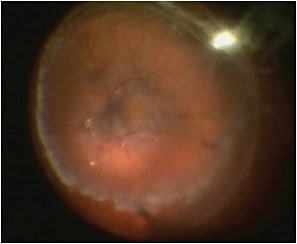

The study was further categorized with regard to PVR stage. Grade A PVR was defined as vitreous haze or vitreous pigment clumping, while Grade B PVR included wrinkling of the inner retinal surface, a rolled edge of a retinal break, or retinal stiffness (Figure 1, page 32). A full-thickness retinal fold, or a star fold in one area, was considered to be Grade C-1 PVR (Figure 2, page 32). PVR ranged from Grade 0 (no PVR) to Grade C-1, and all of the patients had at least three months of follow-up. To our knowledge, this was the largest study of patients with RRD: 181 surgeons from 48 countries provided information on 7,678 RRDs. Most of the results from this study group have already been published.1-4

Figure 1. Intraoperative view with a BIOM of PVR B retinal detachment.